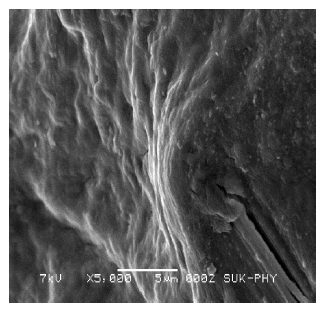

Scanning electron microscopy (SEM)

The SEM of the drug loaded beads was found to be irregular in shape having smooth and dense surface with inward dent and shrinkage due to collapse of the wall during dehydration. The fibrous network was also observed on the surface of the beads as shown in fig. 11-13.

Fig. 13: Scanning electron microscopy (SEM) of ritonavir microbeads with fibrous network

In vitro drug release study